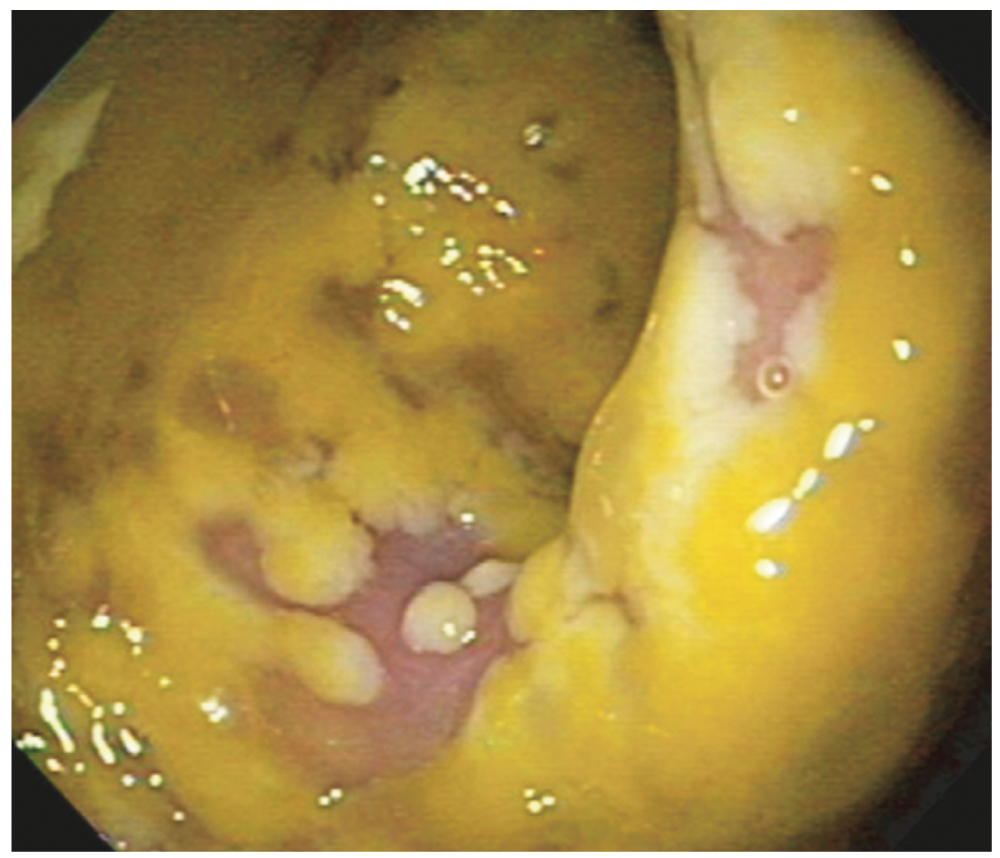

Развившаяся воспалительная реакция может приводить к образованию на поверхности слизистой оболочки кишечника псевдомембран — дискретных жёлто-белых бляшек, которые легко смещаются и в тяжёлых случаях могут сливаться (рис. 1). Они представляют собой микроизъязвления, покрытые плёнкой, состоящей из разрушенных клеток кишечника, нейтрофилов и фибрина. В этом случае речь идёт о развитии псевдомембранозного колита [15, 16]. Наиболее часто поражается дистальный сегмент толстой кишки, а инкубационный период заболевания точно не определён.

Рис. 1. Эндоскопическая картина псевдомембран на поверхности слизистой оболочки толстой кишки (открытый источник).

Fig. 1. Endoscopic picture of pseudomembranes on the surface of the mucous membrane of the large intestine (open source).